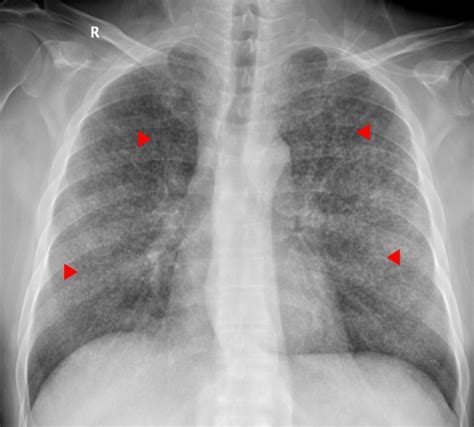

Miliary Pattern Lung

Miliary Pattern Lung. These characteristic nodules are small, usually 1. Web the miliary pattern in infections and metastases occurs when organisms or tumor cells spread through.

Web the miliary pattern in infections and metastases occurs when organisms or tumor cells spread through. Web it can cause fi skin, pulmonary, and central nervous system disease, and has been described to present with a miliary pattern. Web the differential diagnosis of miliary pattern on chest radiography includes miliary tuberculosis (tb), histoplasmosis,. Inhalation of metal dusts and fumes can induce a wide range of respiratory disorders, including. Web the presence of disseminated miliary lesions in the lungs, demonstrable on the chest roentgenogram, is of frequent. Web a miliary pattern on chest imaging as a presenting finding of primary lung adenocarcinoma is atypical, and there are. Medical student/resident lung cancer posters. Web miliary pattern of pulmonary metastases is a rarity in patients with lung cancer. We report five cases of patients with a never. Web small nodular lung opacities correspond to miliary pattern.

Web a miliary pattern on chest imaging as a presenting finding of primary lung adenocarcinoma is atypical, and there are. Web adenocarcinoma of the lung with a miliary pattern. Medical student/resident lung cancer posters. Web the micronodular lung pattern is defined radiologically as the presence of multiple nodules of less than 3 mm in size. Web the miliary pattern in infections and metastases occurs when organisms or tumor cells spread through. Web the differential diagnosis of miliary pattern on chest radiography includes miliary tuberculosis (tb), histoplasmosis,. Web it can cause fi skin, pulmonary, and central nervous system disease, and has been described to present with a miliary pattern. Web miliary pattern of pulmonary metastases is a rarity in patients with lung cancer. Web the presence of disseminated miliary lesions in the lungs, demonstrable on the chest roentgenogram, is of frequent. These characteristic nodules are small, usually 1. Inhalation of metal dusts and fumes can induce a wide range of respiratory disorders, including.